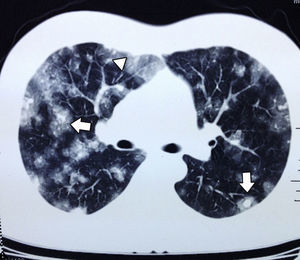

En septiembre presentó hemoptisis y disnea, por lo que se hospitalizo en medio hospitalario particular, en donde se le realizó tomografía axial computada de tórax (fig. 2), broncoscopia con toma de cultivos y biopsias, los cuales fueron negativos a malignidad, tuberculosis o infección fúngica. Se solicita tomografía axial computada de abdomen simple y contrastada donde se muestran lesiones múltiples, redondeadas, hipodensas en el injerto hepático (fig. 3); se toma biopsia guiada por tomografía axial computada, que se reporta negativa a malignidad.

El angiosarcoma se presenta con metástasis tempranas a otros órganos como pulmón, bazo o hueso10. En las radiografías simples de tórax pueden encontrarse infiltrados difusos. Los hallazgos más comunes en la tomografía axial computada de tórax por metástasis de angiosarcoma son las lesiones múltiples sólidas, que cuando se presentan con hemorragia dan una imagen de vidrio despulido, que se conoce como signo del halo y ocurre en el 32% de los pacientes. En menor proporción pueden encontrarse cambios quísticos de paredes delgadas (13%) que cuando se distribuyen en las zonas pleurales aumentan la incidencia de neumotórax o hemotórax12.